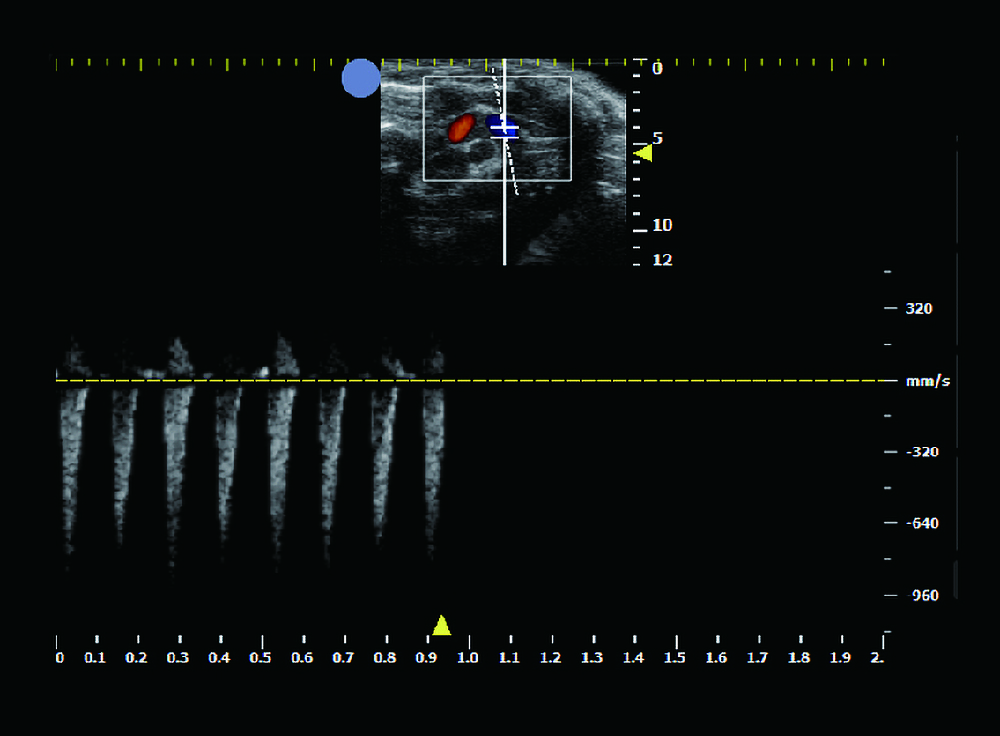

| 兔子 | 450元/样/次 | 包含B超截图+视频+心脏/血管参数分析 | 心脏、主动脉、原位肿瘤测量等 |

| 大小鼠 | 350元/样/次 | 单纯B超截图/视频 |

小动物B超

¥350 - 450